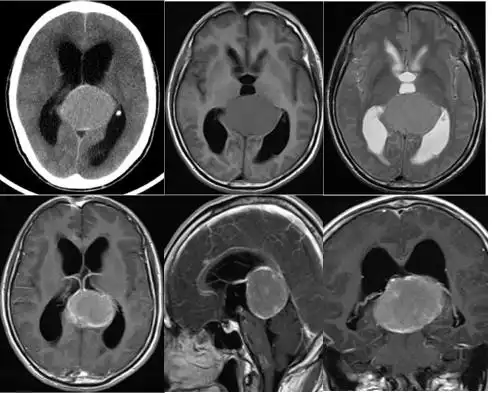

一个月前出现头晕,视力下降,视物模糊,去当地医院就诊,头颅磁共振示

术前核磁共振示左颞长t1,长t2信号占位,强化后边缘呈不规则环形强化.

【病例讨论】血运丰富脑膜瘤 [病例帖]